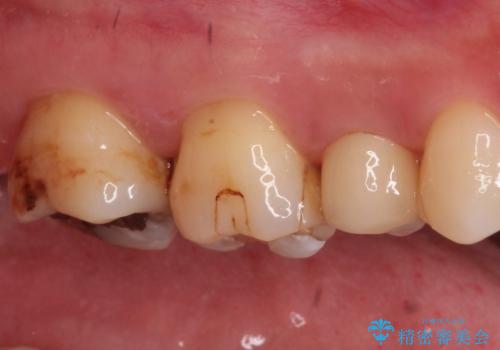

【セラミックインレー】虫歯の治療

- 虫歯を認めたため、セラミックインレーにて治療を行いました。

見た目も綺麗に修復することができ患者様には満足していただきました。

セラミックインレーの接着には必ずラバーダム防湿を行なっています。